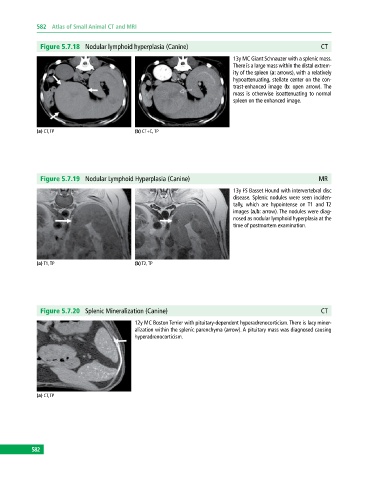

Figure 5.7.18 Nodular lymphoid hyperplasia (Canine) CT

13y MC Giant Schnauzer with a splenic mass.

There is a large mass within the distal extrem

ity of the spleen (a: arrows), with a relatively

hypoattenuating, stellate center on the con

trast‐enhanced image (b: open arrow). The

mass is otherwise isoattenuating to normal

spleen on the enhanced image.

(a) CT, TP (b) CT+C, TP

Figure 5.7.19 Nodular Lymphoid Hyperplasia (Canine) MR

13y FS Basset Hound with intervertebral disc

disease. Splenic nodules were seen inciden

tally, which are hypointense on T1 and T2

images (a,b: arrow). The nodules were diag

nosed as nodular lymphoid hyperplasia at the

time of postmortem examination.

(a) T1, TP (b) T2, TP

Figure 5.7.20 Splenic Mineralization (Canine) CT

12y MC Boston Terrier with pituitary‐dependent hyperadrenocorticism. There is lacy miner

alization within the splenic parenchyma (arrow). A pituitary mass was diagnosed causing

hyperadrenocorticism.

(a) CT, TP